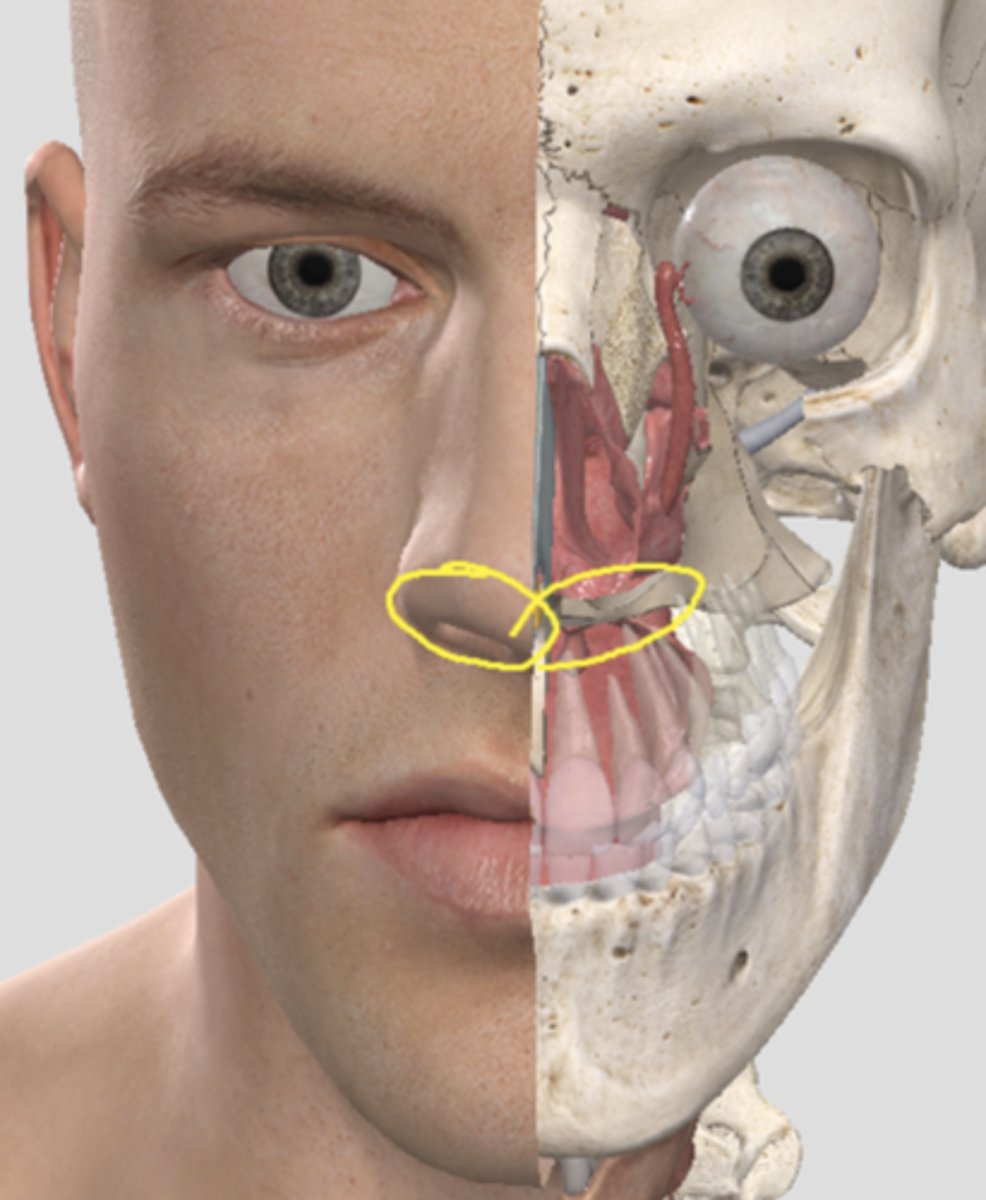

external nares

vestibule

name the circled region

name the circled region

external nares (surface anatomy)

vestibule of the nose (surface anatomy)